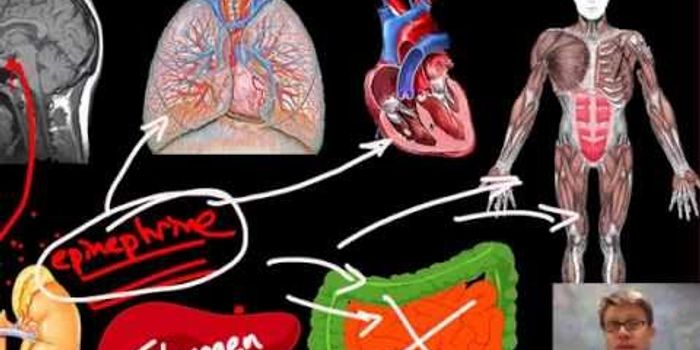

FEB 23, 2019CardiologyThe circulatory system is a complex collection of the heart and its many chambers, and the vessels that move blood aroun ...